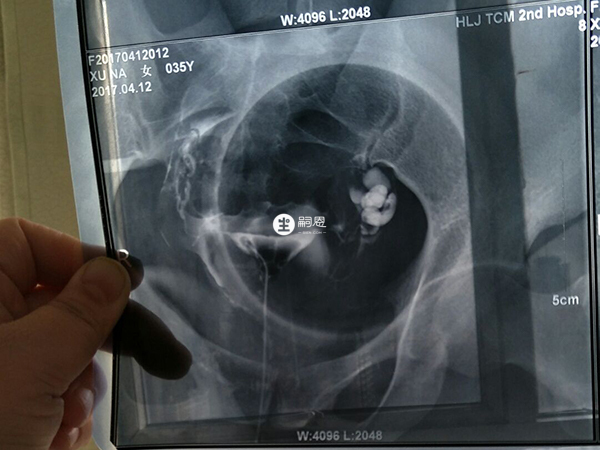

現在檢查雙側輸卵管積水嚴重,準備第二次做試管嬰兒,醫生說我在試管嬰兒移植前需要做結紮手術,請問這個一定要處理嗎?雙側輸卵管積水嚴重的患者,做試管嬰兒在胚胎移植前是一定要處理好積水的,不過不一定就是通過結紮,還可以選擇藥物治療或者是切除輸卵管。藥物治療主要是通過服用阿莫西林、阿奇黴素等抗生素,讓積水慢慢消失,這種方式一般只適用於積水較少的患者。而輸卵管切除適用於情況比較嚴重,沒有自然生育需求的患者。

輸卵管積水指輸卵管傘端阻塞導致輸卵管滲出液積聚形成積液,一般是由於輸卵管炎導致的,如果積水嚴重在試管移植前不做處理,那麼就可能會導致胚胎著床失敗、宮外孕、生化流產等情況,這會直接而影響到輸卵管積水做試管成功率,所以大家在試管移植前一定要做好處理工作,處理方法有以下三種: